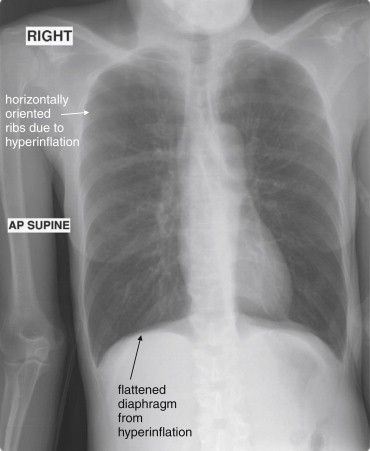

Phase of Respiration: Inspiratory and Expiratory Views

Normally, a chest x-ray is obtained at full inspiration, although in many cases patients may fail to inspire deeply because of chest pain or may be unable to hold their breath in this position because of dyspnea. The chest x-ray captures a frozen, static moment in time, but thoracic structures are actually in motion with patient respiration and cardiac activity. The apparent density of lung tissue varies with the phase of respiration. At end-expiration, lung volumes are very low, the diaphragms appear high, and lung tissue appears dense (whiter). Blood vessels in the lungs appear crowded together, contributing to the apparent density of lung tissue. If the phase of respiration is not considered, this appearance may be mistaken for pulmonary edema. In contrast, a chest x-ray obtained at end-inspiration shows well-inflated lungs, diaphragms that have descended fully, and widely spaced pulmonary vessels. Lung parenchyma under these conditions appears less dense. A clue to the phase of respiration is the number of ribs visible. A rule of thumb is that the diaphragm should lie at the level of the posterior 8th to 10th rib for an adequate respiratory effort in a good-quality chest x-ray. Abnormally dense lung parenchyma such as seen with pneumonia is more visible against the backdrop of fully inflated and lucent (black) lungs. Patients with COPD or asthma may have hyperexpanded lungs with low-density parenchyma and more than 10 ribs visible.